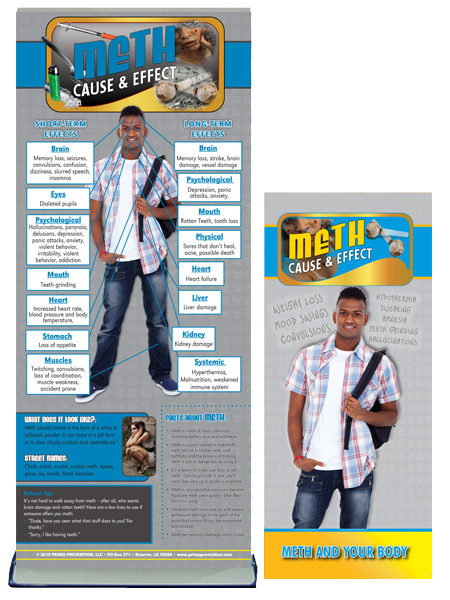

Graphically depicting the grisly effects of methamphetamine on the mouth, this giant mouth display is ideal for schools, law enforcement agencies, and other organizations looking to give teens and young adults compelling reasons to stay away from meth.

The 3-D, handpainted mouth model shows the oral consequences of meth use, such as missing teeth, severely decayed teeth, broken teeth, receding gums, and more. Also includes a tongue model with an ulcer.

Informative text explains how meth harms both the mouth and body and drives home the message that meth is a dangerous drug. 10″ x 10½” x 16½”.